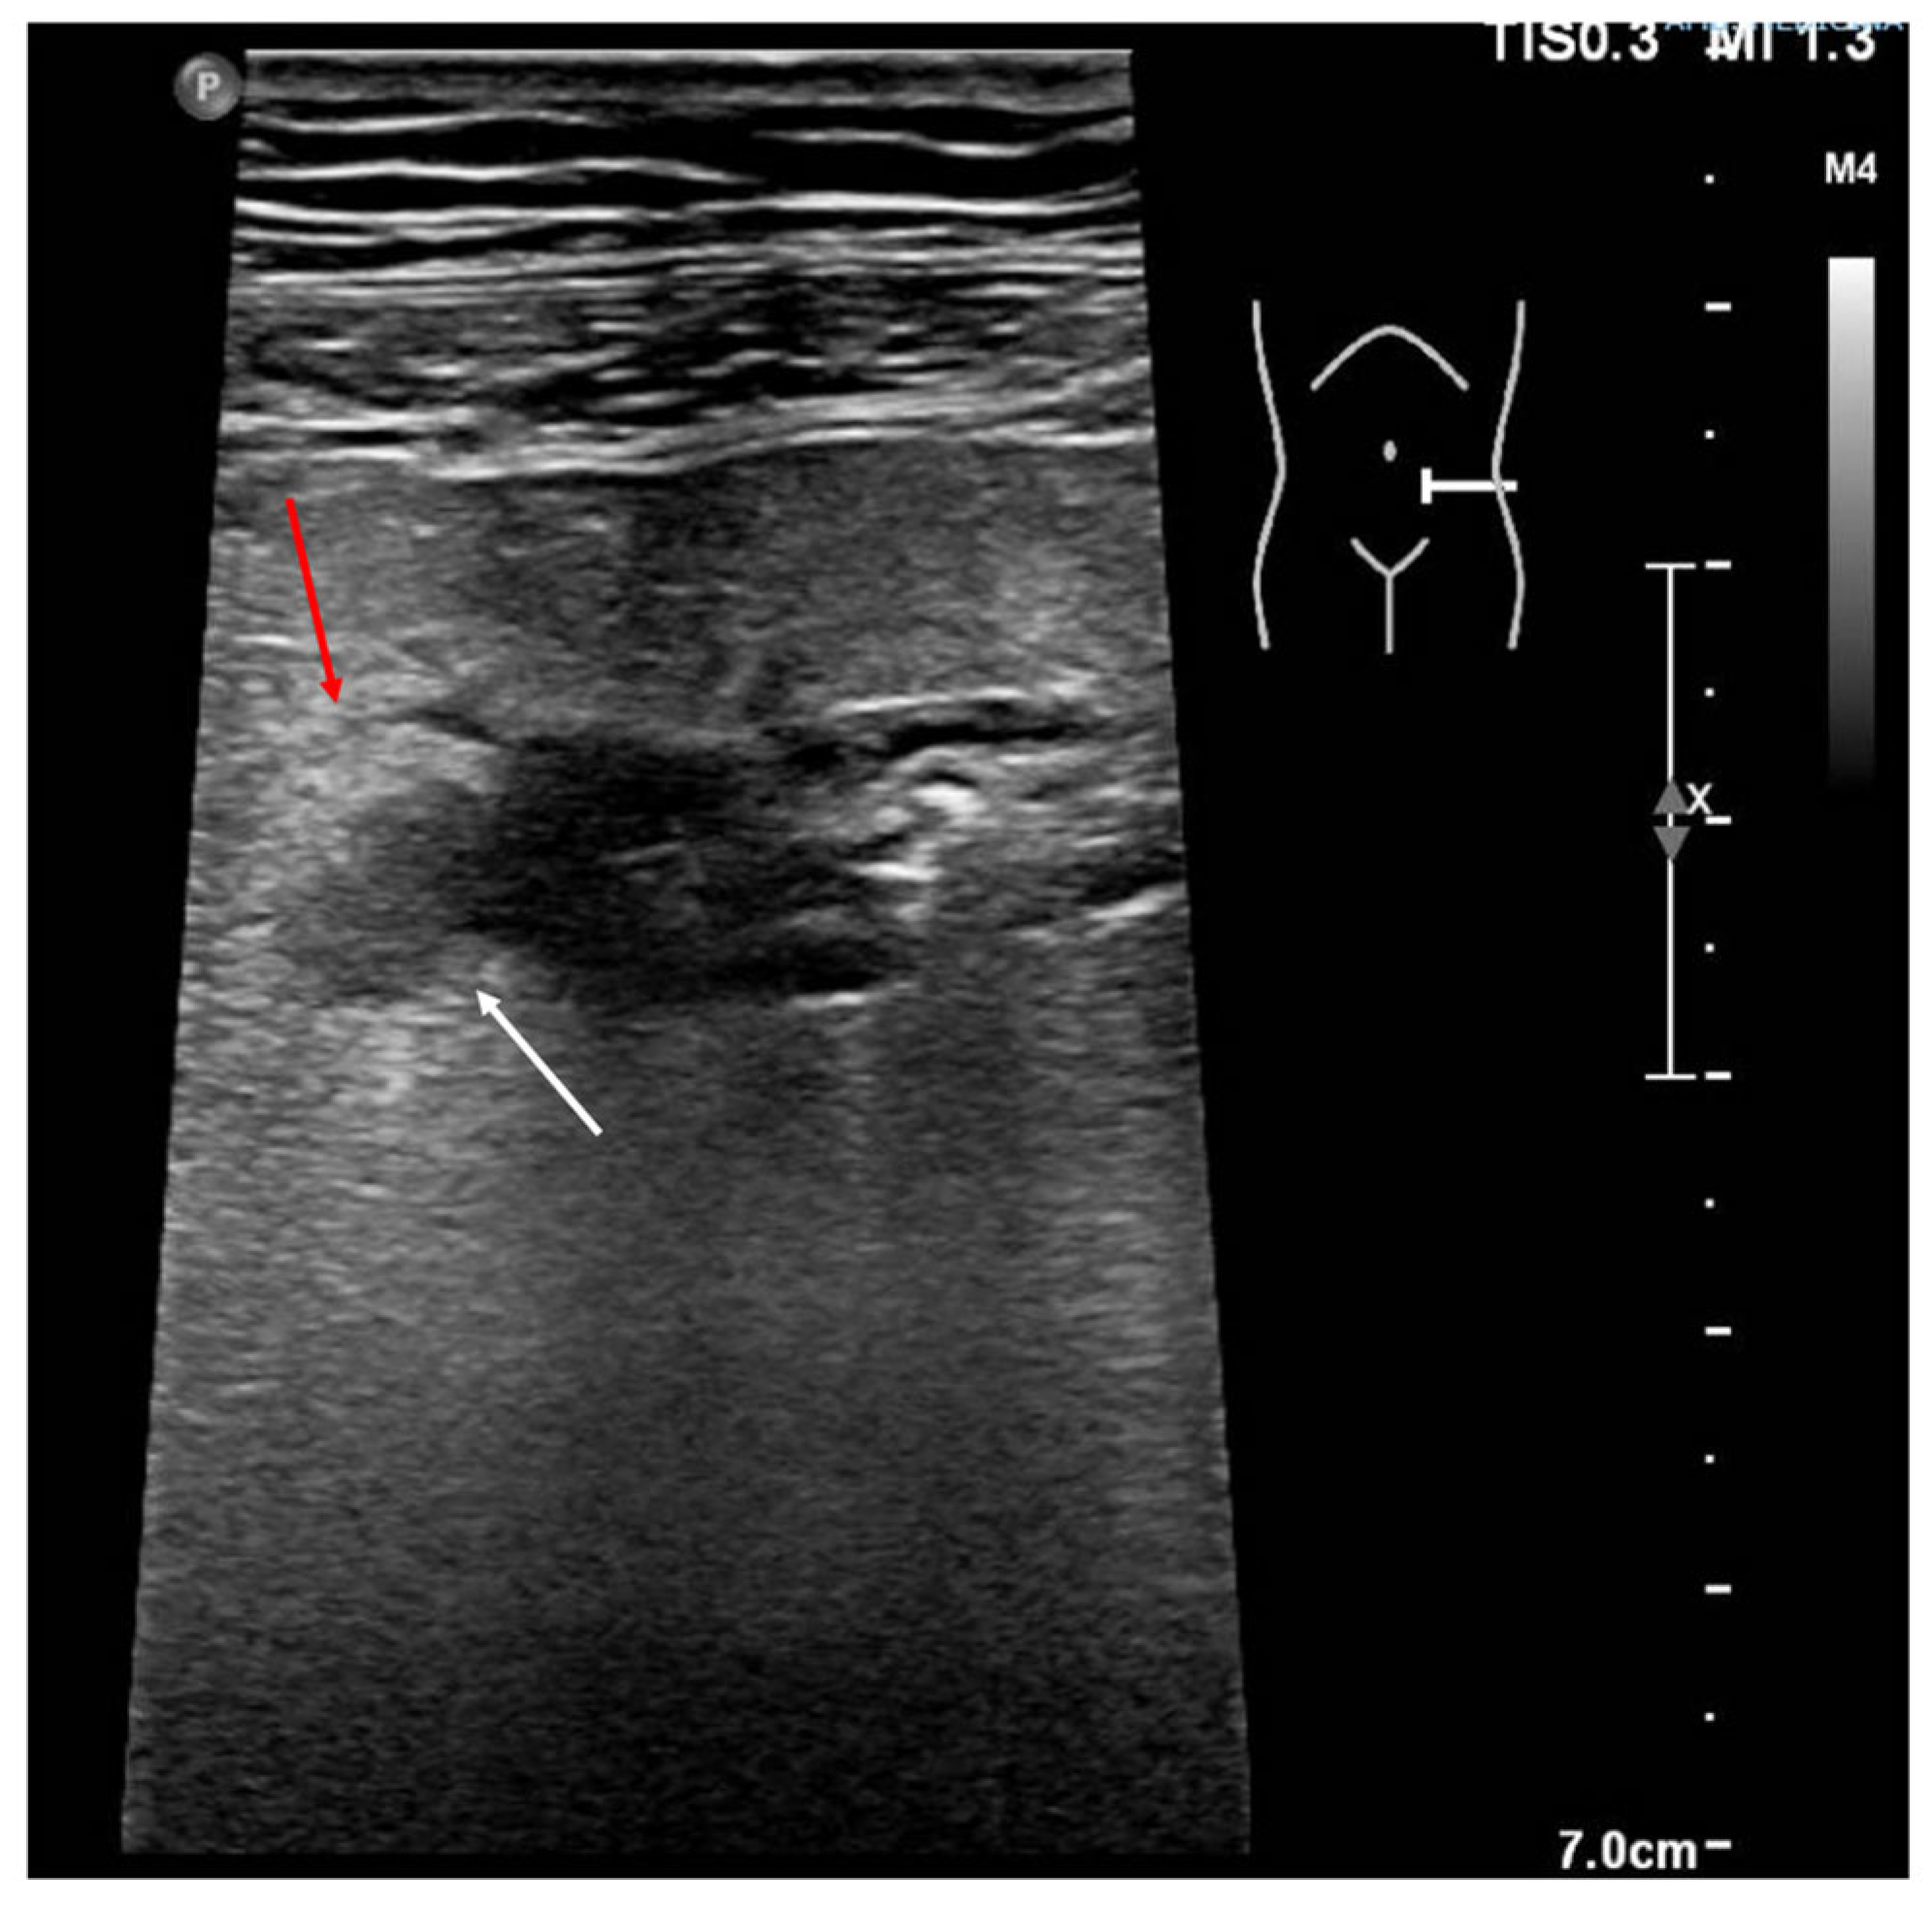

5. Acute Diverticulitis

- Valentino, M.; Serra, C.; Ansaloni, L.; Mantovani, G.; Pavlica, P.; Barozzi, L. Sonographic features of acute colonic diverticulitis. J. Clin. Ultrasound. 2009, 37, 457–463. [Google Scholar] [CrossRef] [PubMed]